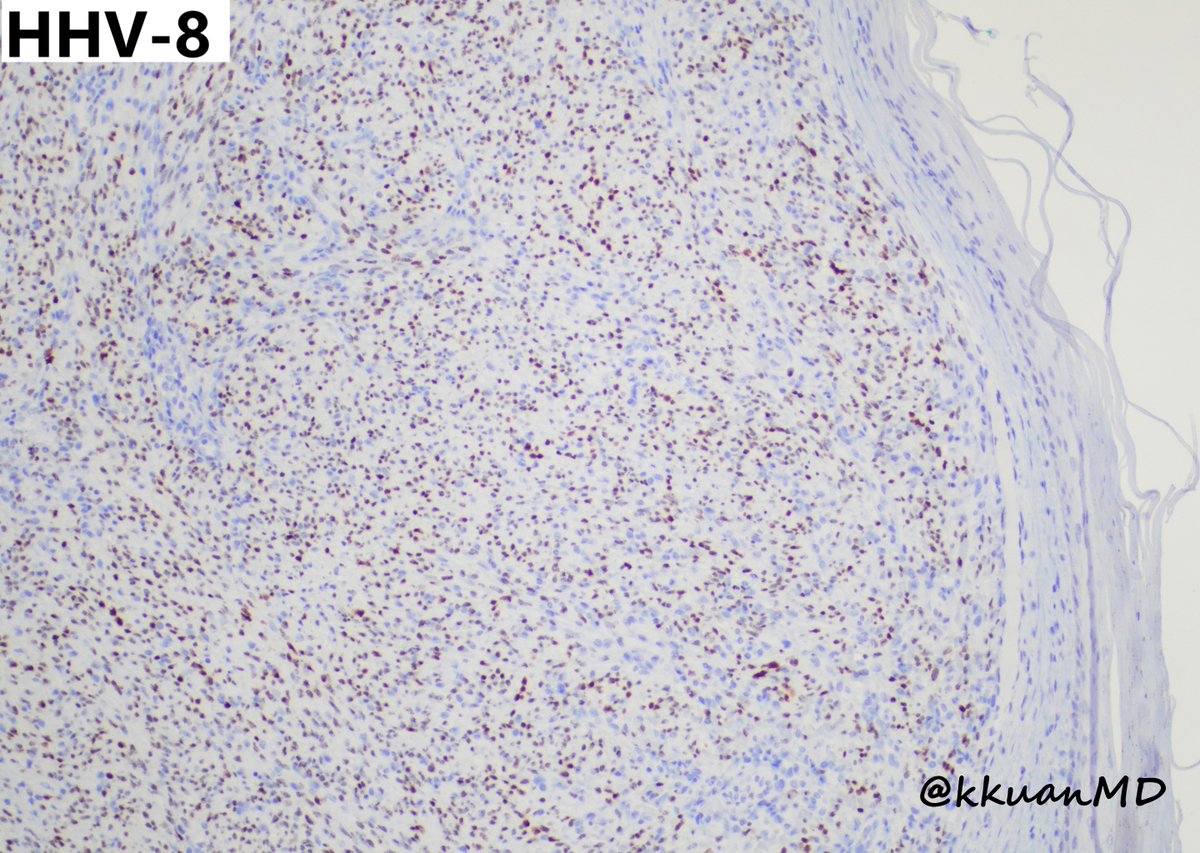

Cutaneous Kaposi sarcoma from 35yo M with HIV/AIDS #PathTwitter #pathology #dermpath #dermtwitter #patheducation #infectiousdisease Einstein Montefiore Pathology the New York Pathological Society Brian Cox, MD, MAS Anju Pandey Rebecca M. Marrero Rolon Rebecca Czaja Jerad Gardner, MD Tristan Rutland MBBS FRCPA IFCAP Olaleke Folaranmi